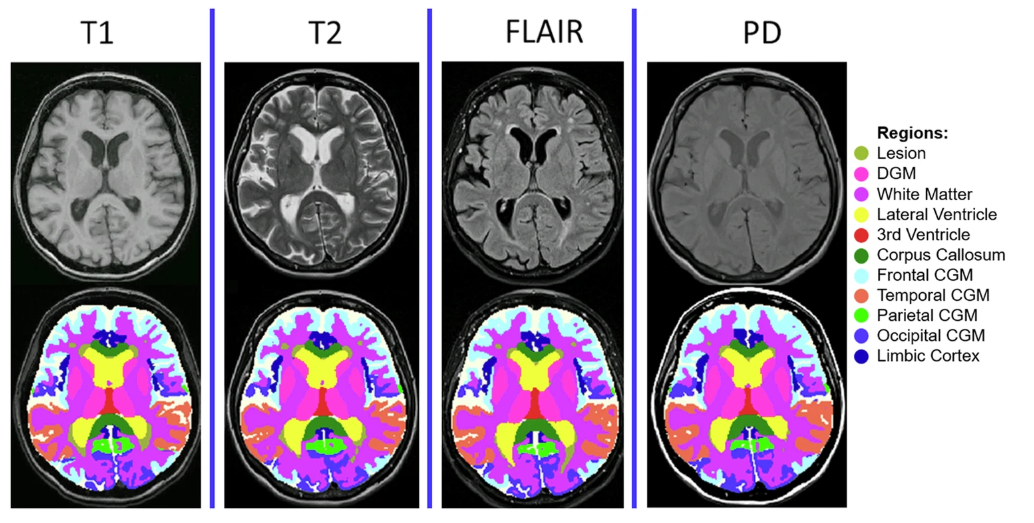

*MindGlide 通过医院档案中常用的 MRI 对比和相关组织强度(T1-weighted、TI-weighted、Proton Density (PD) 和 T2-Fluid Attenuated Inversion Recovery (FLAIR))处理 MRI,包括 2D 和 3D 扫描。

在检测脑组织损失的治疗效果中,MindGlide 显示了治疗组皮质 GM 体积损失率明显低于安慰剂组。 下图为各种对比的分割示例。